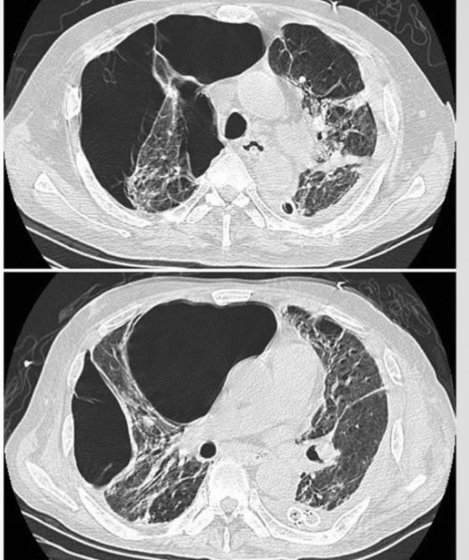

?

Are the black areas filled with air on diagnostic imaging

• Take up a lot of dead space and prevent full exhalation

• Treatment with thoracoscopic bullectomy; volume reduction surgery with localized area of ___; lung transplant with larger areas

A

Bullae

The lung with COPD

• Hyperinflation of the lung (air is darker than lung tissue)

• Increased space between ribs

• Less of an angle in the bases; the diaphragm forced down and ribs are forced up and out. Similar to inspiratory position at rest

• Patient has difficulty taking a deeper breath and needs to force an exhalation. One way to release trapped air is pursed-lip breathing